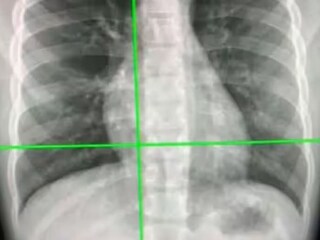

এই পরিস্থিতিতে কোভিড নির্ণয় খুবই গুরুত্বপূর্ণ, চিকিৎসা এবং সংক্রমণ রোধের ক্ষেত্রে। অস্ট্রেলিয়ান গবেষকরা সম্প্রতি দাবি করেছেন, একটি AI সিস্টেম তাঁরা তৈরি করেছেন যা, ৯৮ শতাংশের বেশি সঠিক ভাবে বুকের এক্স-রে থেকে কোভিড-১৯ সনাক্ত করতে পারে। এই পরীক্ষাই সর্বাধিক দ্রুত বলে দাবি।

বুকের এক্স-রে বহনযোগ্য, সর্বত্রই পাওয়া যায় এবং সিটি স্ক্যানের তুলনায় আয়নাইজিং বিকিরণের এক্সপোজারও কম। ফলে এটা খুবই উপকারী হতে চলেছে বলে দাবি গ্যান্ডোমির।

সায়েন্টিফিক রিপোর্ট জার্নালে প্রকাশিত গবেষণাপত্রে জানান হয়েছে, কাস্টম কনভোল্যুশনাল নিউরাল নেটওয়ার্ক (Custom-CNN) নামক একটি ডিপ লার্নিং অ্যালগরিদম ব্যবহার করা হয়েছে এই সিস্টেমের জন্য।